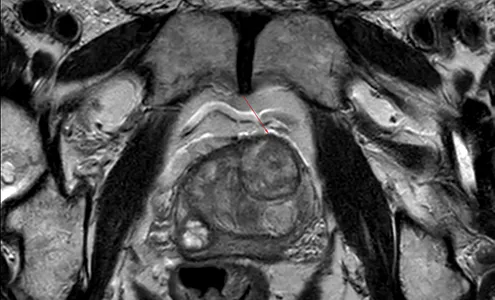

https://news.atos-kliniken.com/wp-content/uploads/2025/09/Rother-vorschau.webp300495ATOS xbhttps://news.atos-kliniken.com/wp-content/uploads/2020/12/atos-news-2.pngATOS xb2025-10-13 09:00:152025-09-25 10:42:44Prostata-MRT: Eine essenzielle Vorsorgeuntersuchung für Männer